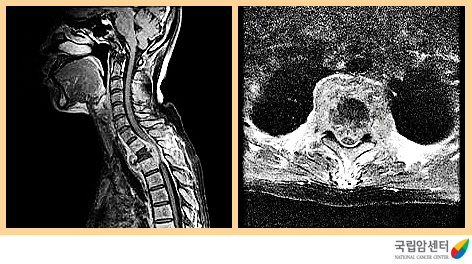

[ 전이성 척수종양의 자기공명 영상촬영 소견 ]